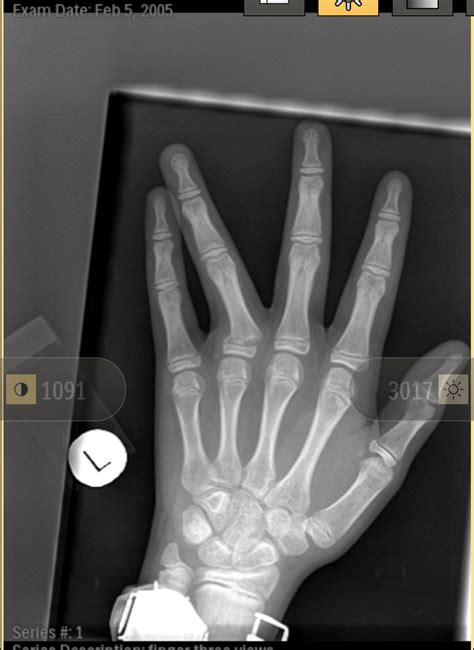

Diagnosing a dislocated pinky finger typically involves a physical examination and imaging tests. The doctor will:

• Examine the finger to assess the extent of the injury.

• Order X-rays to confirm the dislocation and rule out any fractures.

In some cases, additional imaging tests like an MRI or CT scan may be required to get a more detailed view of the injury.

• dislocated pinky finger xray